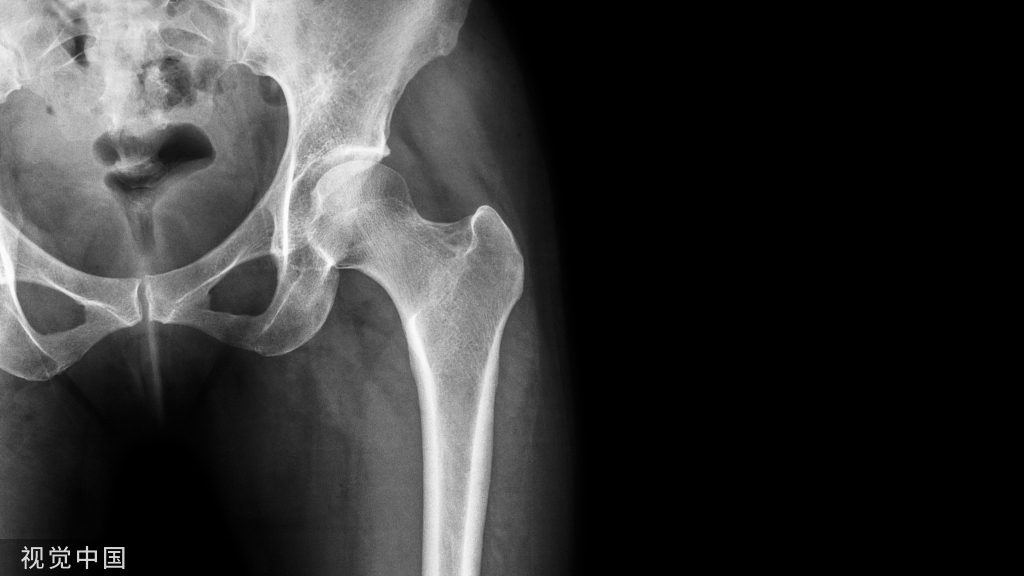

人工关节翻修术,国内最初曾称为修正术、翻修术等,它是指人体关节行人工关节置换术后,因各种原因出现松动、下沉、磨损、感染等改变,需再次手术进行新的关节置换手术而言。